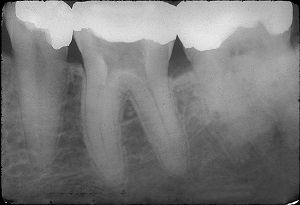

Dentaltown has published the longest case history ever reported in dental literature. The 70-year recall of a vital calcium hydroxide pulpotomy performed by Harold Berk, DDS in 1946 was reported in the February 2017 issue and appears online. The article shows the step-by-step technique for the surgical procedure.

Vital pulpotomy is the amputation of the coronal pulp tissue and placement of a pulpal dressing with the intention of maintaining the vitality of the radicular pulp. Dr. Harold Berk, a pioneer and early researcher in pulp biology and vital pulp therapy, reported on the 50-year recall of his first human pulpotomy (1996) in his book, Save That Tooth. Dr. Ali Maddahi saw the patient in 2016 and is the lead author of the 70-year report.